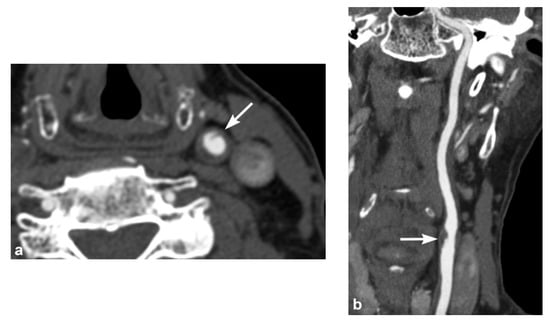

2. Imaging Techniques

3. Imaging Findings of Arterial Injury